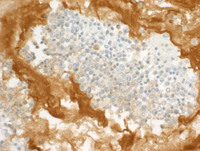

Figure 6: MUM1, Kappa, & Lambda in Primary Effusion Lymphoma

Additionally, they are positive for MUM1 (a plasmacytic marker) with suggestion of weak kappa light chain expression in some cells (lower left image) while lambda is negative.